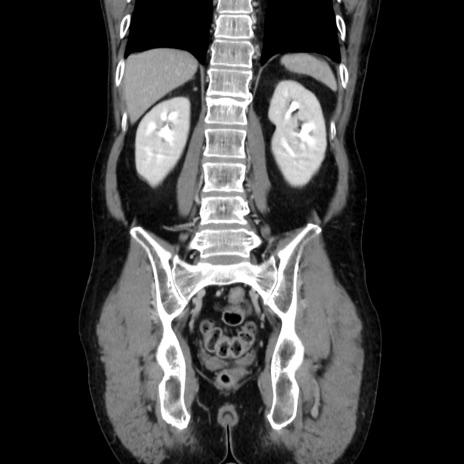

症例37(冠状断像)

【症例】40歳代 男性

【主訴】腹痛

【現病歴】4時間ほど前に電車に乗車中に臍部上より腹痛出現。徐々に増悪し起立困難となり、救急外来受診。生ものは数日食べていない。今朝お雑煮を食べた。

【身体所見】BT 36.8℃、BP 117/84mmHg、HR 91/min、SpO2 97%、苦悶様、腹部:臍上部広範囲圧痛あり、反跳痛±

【データ】WBC 8100、CRP 0.03